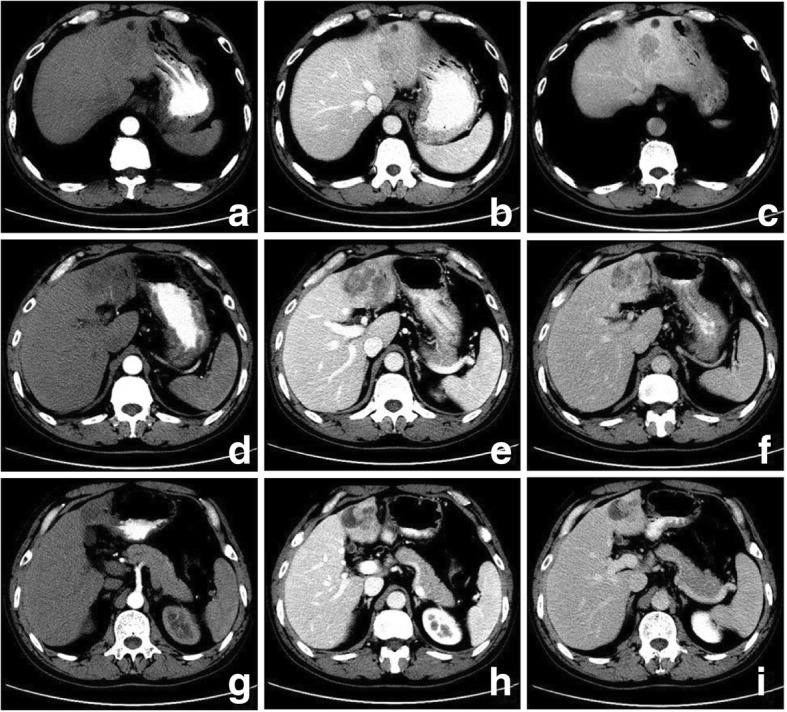

Fig. 1.

Sarcomatous intrahepatic cholangiocarcinoma in a 47 year-old man. The axial CT scans display a hypovasular mass with intratumoral hemorrhage (a-d). The bisected specimen displays a large solid tan mass with hemorrhage and necrosis breaching the liver capsule without complete penetration (e). Hematoxylin and eosin (H & E) stain shows multifocal hemorrhage and necrosis. Hemosiderosis is found (f)

Table 2 shows pathologic features of the study population. Of the seven surgically resected tumors, the hemorrhage (three cases) and different degrees of necrosis (six cases) were found (Fig. 1). Complete and partial capsules were identified in S-ICC (Fig. 2) and S-HCC-CC respectively. Five cases involved the liver capsules (Fig. 1) with two of them (S-ICC and S-HCC) rupturing into the perihepatic space. Additional findings were vascular thrombosis (four cases), adjacent organ invasion or seeding (two cases), satellite nodules or intrahepatic metastasis (two cases), and lymph node metastasis (two cases).

Regarding the distribution of enhancement, peripheral enhancement was seen in 2 S-ICCs and 3 S-HCCs (Fig. 3). Mix rim and internal heterogeneous enhancement (Fig. 4) was found in 2 S-HCCs, internal heterogeneous enhancement was shown in 2S-HCCs and 1 S-HCC–CC (Fig. 6), and no homogeneous pattern was observed. Eight tumors including 2 S-ICCs, 5 S-HCCs and 1 S-HCC–CC were hypo-vascular (Figs. 1, 2, 3 and 4) and the remaining 2 S-HCCs mainly presented hyper-intense enhancement on the arterial phase. As to the enhancement degree of the solid part in the tumor, six tumors showed hyper enhancement compared to the background liver.

With respect to the dynamic pattern of enhancement, of the ten tumors, 40% with 2 S-HCCs and 2 S-ICCs showed peripheral enhancement on the arterial phase and progressive enhancement towards the center (Fig. 2) on the later phases, 20% with 2 S-HCCs showed heterogeneous enhancement on the arterial phase and progressive or persistent enhancement on the later phase (Figs. 2, 3, 4 and 5), and 30% with 3 S-HCCs presented obvious peripheral and heterogeneous enhancement on the arterial phase and then wash out peripherally and partially on the later phase, mimicking ordinary HCC. The remaining S-HCC–CC exhibited a variable enhancement character for its multinodular change (Fig. 6). The tumor showed mild inhomogeneous enhancement on the arterial phase, and the portion near the subcapsular area of the tumor showed persistent thin rim enhancement accompanied by an mural nodular on the portal and equilibrium phase, next to the cyst change was the mild to moderate progressive fill-in enhancement, and the upper portion presented washout on the equilibrium phase.

Our study demonstrated that PHSC generally presented hypovascularity seen as peripheral enhancement on the arterial phase imaging. The PHSC was characterized by the peripheral viable cancerous tissue with fibrous stroma and central necrosis or hemorrhage [14, 26]. Similar to prior results [6, 15], the necrosis was more frequently seen with a high frequency of 85.7% (six of seven) in the surgically resected tumors in our study. The poorly differentiated cells of the sarcomatoid component grew so rapidly that the neovasculature could not adequately supply the fast-growing malignant cells, resulting in the central necrosis. In additional to the peripheral ring enhancement, when the necrosis was accompanied by fibrous septum or was scattered, the tumors might exhibit heterogeneous enhancement distribution such as a mix of rim and internal or internal only heterogeneous enhancement as shown in our study.